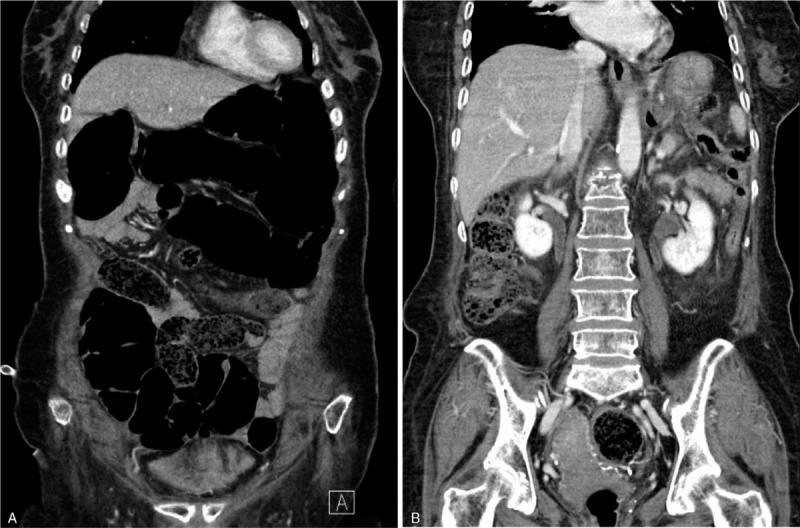

A 76-year-old woman with a 40-year history of type 2 diabetes mellitus (DM), for which metformin (1000 mg/day) and dapagliflozin (10 mg/day) were prescribed, presented with malaise, fever, and oliguria. On presentation, her white blood cell count (11,800/μL), serum creatinine (3.2 mg/dL), and C-reactive protein (54 mg/L) were abnormal. Bilateral pyeloureteritis and diffuse paralytic ileus were present. She received intravenous antibiotics and total parenteral nutrition, and was asked to fast. Her renal function and ileus briefly improved. Oral hypoglycemic agents, metformin and dapagliflozin, along with enteral feeding were reinstituted on day 3 of hospitalization. However, on day 6 of hospitalization, the patient developed an altered state of consciousness including confusion, lethargy, and stupor. Several laboratory abnormalities suggestive of ketoacidosis with euglycemia were noted.

The patient was diagnosed with eu-DKA accompanied by severe hypernatremia (corrected serum Na concentration, 163 mEq/L) and hypokalemia following dapagliflozin re-administration.

一名76岁女性,有40年2型糖尿病病史,正在服用二甲双胍(1000毫克/天)和达格列净(10毫克/天),出现不适、发热和少尿症状。就诊时,她的白细胞计数(11,800/μL)、血清肌酐(3.2毫克/分升)和C反应蛋白(54毫克/升)异常。存在双侧肾盂输尿管炎和弥漫性麻痹性肠梗阻。她接受了静脉抗生素治疗和全胃肠外营养,并被要求禁食。她的肾功能和肠梗阻症状短暂改善。住院第3天重新开始使用口服降糖药二甲双胍和达格列净以及肠内营养。然而,住院第6天,患者出现意识状态改变,包括意识模糊、嗜睡和昏迷。发现了一些提示正常血糖性酮症酸中毒的实验室异常。

重新使用达格列净后,患者被诊断为eu-DKA,伴有严重高钠血症(校正血清钠浓度为163毫当量/升)和低钾血症。